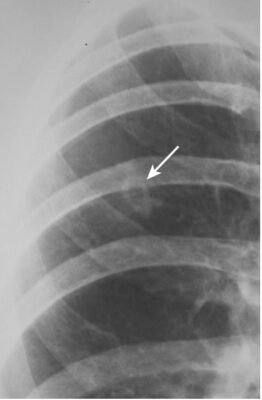

- Bệnh vùng khoang chứa khí có thể có hình ảnh phế quản chứa khí /(khí phế quản đồ)(air bronchogram).

- Khả năng nhìn thấy không khí trong phế quản vì bệnh lý khoang chứa khí xung quanh được gọi là hình ảnh phế quản chứa khí

- Hình ảnh phế quản chứa khí là một dấu hiệu của bệnh lý khoang chứa khí.

- Bình thường không nhìn thấy được phế quản vì thành của chúng rất mỏng, chứa không khí và được bao quanh bởi không khí. Khi một thứ gì đó như chất dịch hoặc mô mềm thay thế không khí bình thường bao quanh phế quản, thì không khí bên trong phế quản trở nên có thể nhìn thấy dưới dạng một loạt cấu trúc hình ống phân nhánh, màu đen – đây là hình ảnh phế quản chứa khí (Hình 3).